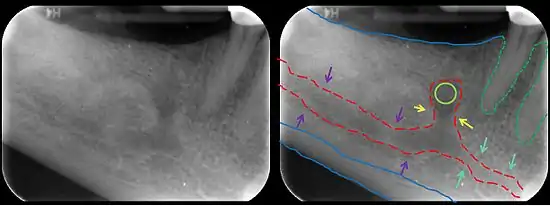

![]() The mandibular incisive canal (indicated here by coral green arrows) continuing anteriorly (to the right) from the mandibular canal (purple arrows) after the mental foramen (light green circle). | |